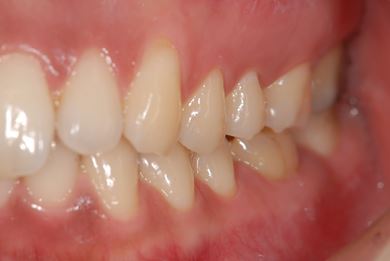

インプラントの症例写真 IMPLANT

インプラント治療

| 主訴 | 銀歯がはずれた奥歯にひびが入っており、抜歯しなければいけないため、インプラントの治療相談を希望。 | ||||||||||||||||||||||||||||||||

| 治療内容 | インプラント1本、メタルボンドセラミック1本 | ||||||||||||||||||||||||||||||||